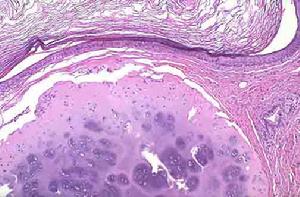

2.鏡下所見 腫瘤由許多內皮細胞形成的擴張淋巴管組成,管內為淋巴液,內有少量淋巴細胞。